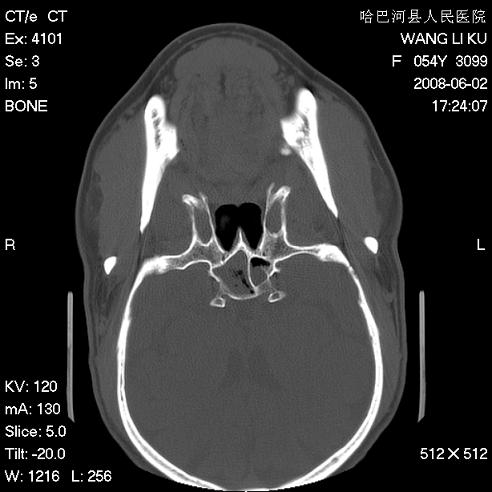

标题: CT13803:反复性鼻塞、流涕一年余 [打印本页]

标题: CT13803:反复性鼻塞、流涕一年余

副鼻窦炎,右上额窦积脓。左眼肌锥内见致密影,视神經受压

1.全组副鼻窦炎2.双侧上颌窦积液

1)全副鼻窦炎(左侧上颌窦黏膜下囊肿或息肉)。2)左眼眶肌锥内不规则小结节状软组织密度影;考虑为小血管瘤可能。建议行ct增强扫描检查。

全组副鼻窦炎,左侧肌锥内不规则形软组织肿块影,与眼外肌密度相当,左侧视神经受压,肿块与视神经及眼外肌分界清晰,眼外肌无增粗,眶壁无破坏,球后脂肪间隙不模糊,考虑良性改变,小血管瘤或神经源性肿瘤可能,建议增强扫描。

谢谢,增强扫描做了,眶内病灶与海绵窦同步明显强化,血管瘤